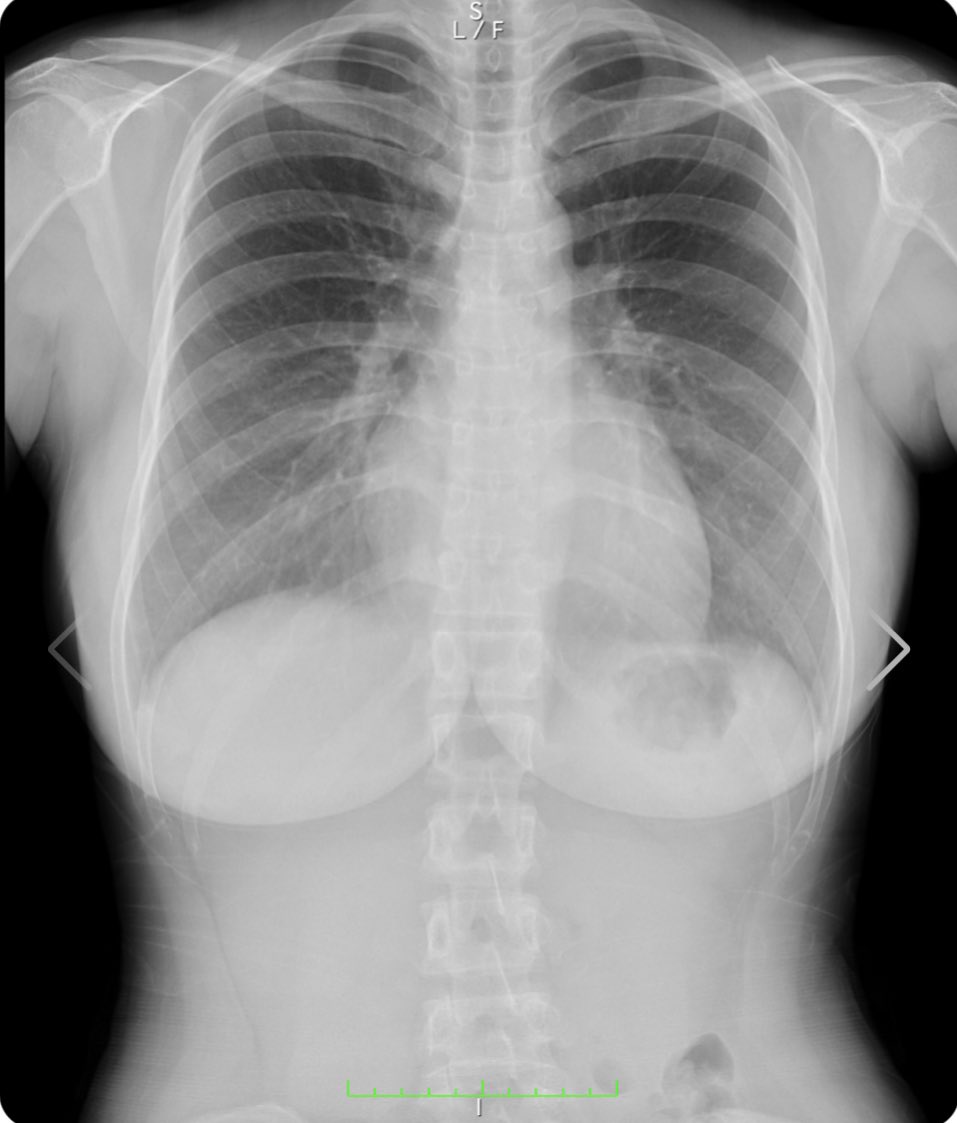

人気爆乳グラドル天木じゅん、スケスケの丸見えオッパイを解禁し偽乳疑惑を払拭するww グラビア天木じゅん 2021年8月21日 7:07 17コメント Tweet ※当サイトはアフィリエイト広告を利用しています 似ている人気記事 バスト約100cm美少女ちとせよしの、紐タイプのハイレグ衣装でえちえちなバニーコスプレに挑戦しほぼ裸の格好にww 長身×巨乳×美脚の現役バニーガール 蜂羽レム、店から黙って拝借したバニーコスを着てノリノリAVデビューwww 名門ミスコン「ミスマガジン」2021~2023の3世代・18名が大集合、個性溢れるビキニ姿を見せてるww ertkな名無し レントゲンでもわかるエロいおっぱい 私の胸部レントゲン!www正面から見た写真の右の胸の黒いのは胃泡だよ安心してね裸を通り越して私の骨と脂肪を見れたあなたには幸運が訪れると信じてます❤️(私の胸は遺伝です)w#1mmでもいいなと思ったらRT #胸部レントゲン #人間ドック pic.twitter.com/OmgFNaRvui— 天木じゅん (@jun_amaki) August 18, 2021 ertkな名無し 医者になればオッパイのレントゲン見放題か・・ ertkな名無し これは本物 小池栄子様♀️♀️♀️#1mmでもいいなと思ったらRT #天木TikTok pic.twitter.com/8vkmhu0LD2— 天木じゅん (@jun_amaki) August 9, 2021 ertkな名無し 綺麗な肺ですね まさにフルヌード 撮影頑張ってきます♥︎#1mmでもいいなと思ったらRT pic.twitter.com/BO6j7hkZqW— 天木じゅん (@jun_amaki) August 10, 2021 9th DVD『じゅんちゃん♡』絶賛予約受付中https://t.co/F94nYpmxMOオフショットだよっっ#1mmでもいいなと思ったらRT pic.twitter.com/76ljB26SHC— 天木じゅん (@jun_amaki) August 15, 2021 天木じゅん 最新作 https://www.dmm.com/mono/dvd/-/detail/=/cid=n_701tsds42550tk/ サンプル再生 こちらの「サンプル再生」でも見れます 天木じゅんの関連記事:アンテナからエロチカ記事へのリンク 天木じゅんが初DVDでIカップの爆乳使ってパイズリwww 枕営業が話題の仮面女子が冠番組でスク水で入浴百合プレイwww 仮面女子天木じゅんのHカップ爆乳使った隠し芸が卑猥すぎwwwwww コメント 通りすがりの紳士:2021/8/21 7:34 アッハイ 通りすがりの紳士:2021/8/21 8:35 おっぱい 通りすがりの紳士:2021/8/21 8:47 問題は乳じゃないんだっていい加減気付けよ。 通りすがりの紳士:2021/8/21 8:50 天木じゅんがどうとかいうわけじゃなくレントゲンなんて何の意味もないぞ シリコンバッグじゃなくて脂肪注入じゃレントゲンでわからんからな 昔はペチャパイだった、ほしのあきが偽乳疑惑かわすためにTVの企画ですでにやってる。 通りすがりの紳士:2021/8/21 10:24 ぶち込みたいわ 通りすがりの紳士:2021/8/21 10:41 俺はずっと信じてたぜ!じゅんちゃんの唯一の存在意義は乳袋なのにそれで嘘つくわけないよ! 通りすがりの紳士:2021/8/21 11:04 >>6 拾い物って言葉知ってる?残念だけど偽乳って周りが認識してしまったらそれはもう偽乳なの 同じカップ数なら柳瀬さきのが至高ですよ? 通りすがりの紳士:2021/8/21 11:21 流石にこれが偽乳と言うのは無理があるよなw 通りすがりの紳士:2021/8/21 11:26 ぶち込みたいわ、 通りすがりの紳士:2021/8/21 11:33 >>8 お前の思考に無理がある() 通りすがりの紳士:2021/8/21 16:36 最近は脂肪吸引したもの以外にも、ヒアルロン酸をうつ豊胸もあります。 効果の時間は脂肪吸引より短いですが、メスを使わないので安全ですし 写真集を出す前とかに少しボリュームをアップするのに効果があります。 通りすがりの紳士:2021/8/21 18:43 顔がねぇ 通りすがりの紳士:2021/8/21 19:08 ※12 キモメンのお前が言える顔じゃねえだろ 通りすがりの紳士:2021/8/21 19:56 ていうか今回はアイドル学園公式サイトではサンプル画像無いのね…ひそかに楽しみにしてたのに… 通りすがりの紳士:2021/8/21 20:19 高濃度乳腺 通りすがりの紳士:2021/8/21 21:16 ※13 一般人とアイドル比べてどうすんのw 通りすがりの紳士:2021/8/22 13:27 偽乳じゃない証明ならレントゲンじゃなくブラックライト照らせば一発でわかるのにw 静止画だと解りづらいが動画だと顔が不自然なのが解る。 コメント Δ 日本語が含まれない投稿は無視されますのでご注意ください。(スパム対策)

天木じゅんがどうとかいうわけじゃなくレントゲンなんて何の意味もないぞ

シリコンバッグじゃなくて脂肪注入じゃレントゲンでわからんからな

高濃度乳腺